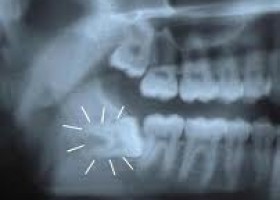

Wisdom teeth, otherwise known as third molars, are the last set of teeth to develop. Sometimes one or more of these third molars fails to emerge in proper alignment or fails to fully emerge through the gum line and becomes entrapped or "impacted" between the jawbone and the gum tissue. Impacted wisdom teeth can result in swelling, pain, and infection of the gum tissue surrounding the wisdom teeth. In addition, impacted wisdom teeth can cause permanent damage to nearby teeth, gums, and bone and can sometimes lead to the formation of cysts or tumors that can destroy sections of the jaw. Therefore, dentists recommend people with impacted wisdom teeth have them surgically removed.